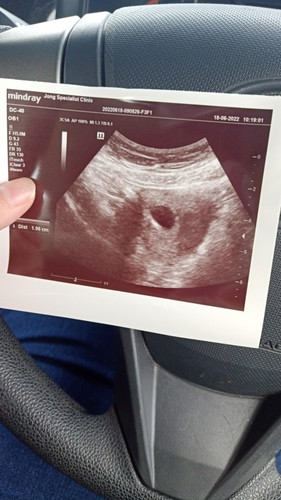

7 weeks 6 days scan

Tahniah sis🤗Normal tu sis, baby memang belum nampak lagi, 8 weeks baru nampak badan baby yg kecil. Yang di dalam kantung tu should be the heart yg baru develop. Sepatutnya boleh nampak and dengar its pumping sudah. Kat klinik swasta boleh dengar dah sis

ada tanya tak anggaran usia kandungan melalui saiz kantung ? ni scan kat kk ke? kalau boleh try scan kat swasta , tanya anggaran usia ikut saiz kantung tu 🤗 sebab saya 8w , saiz kandungan saya 7w1d masa saya scan bulan lepas 🤗